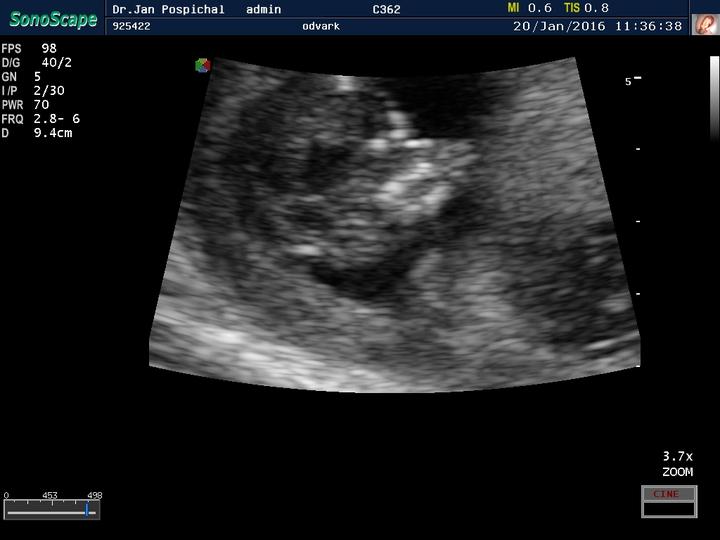

Zdravim, tak dnes kontrola u dr, Sebik je v pořádku akorad trošku cvalik 😀 ve 32tt vazime 2100g takze zadnej drobecek 🙂 a kolik vazi Vase stesticka?

Zdravím Vás dámy 🙂 tak dnes kontrola 20+1tt a už nám potvrdili že budeme 100% chlapák 🙂 fotečku bohužel nemám, mám video ale to netušim jak se sem dává 🙂 vše je v pořádku a rosteme jako z vody... délka od hlavičky k zadečku 15cm a váha 400g... už ted se těšim až náš poklad zase uvidim 🙂